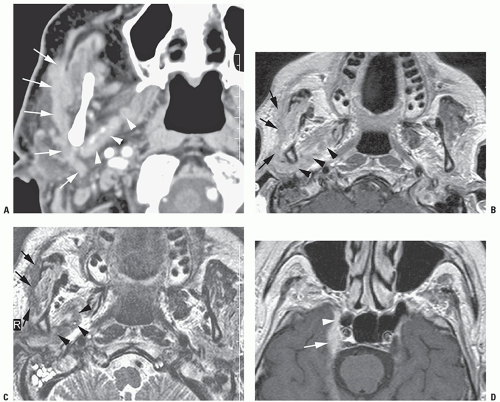

External Ear Disease

External Ear disease Source : www.slideshare.net